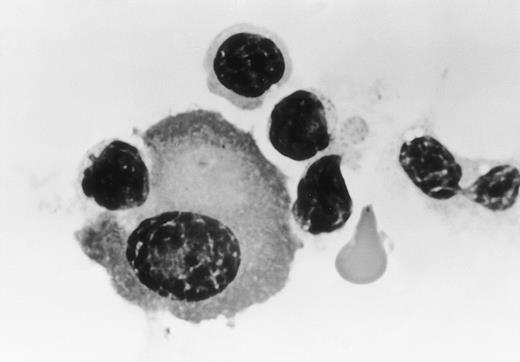

Morphological examination showed that these myeloma cells were attached to large granular lymphocytes, and cytolysis of myeloma cells was only observed in the presence of humanized anti-HM1.24 MoAb (Fig4). In contrast, no cytolysis of HEL cells was seen with humanized anti-HM1.24 MoAb.

Morphology of effector cells attacking myeloma cells. Myeloma cells were purified from the bone marrow (patient no. 1) and were cultured with PBMCs from a healthy donor in the presence of humanized anti-HM1.24 MoAb (1 μg/mL) for 30 minutes. Cytospin preparations were stained with Wright-Giemsa (original magnification × 330).